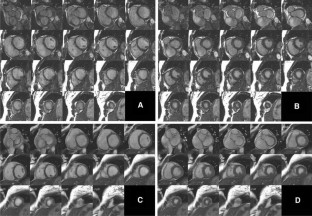

Fig. 1

Fig. 2

Fig. 3

Fig. 4